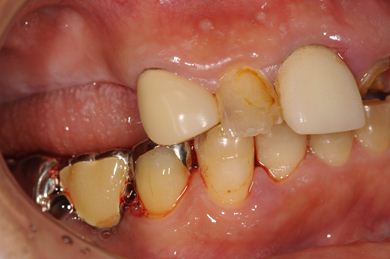

| 性別/年齢 | 男性 / 58歳 | ||||||||||||||||||||||||||||||||

| 主訴 | 上前歯欠損部のインプラント治療を希望。 | ||||||||||||||||||||||||||||||||

| 治療方針 | 右上奥はソケットリフトにて上顎洞拳上してインプラント埋入を可能にし、上顎前歯部は骨再生法によりインプラント治療を行う。その他、補綴により口腔内全体の機能的審美的回復を行う。 | ||||||||||||||||||||||||||||||||

| 治療内容 | インプラント8本(GBR、ソケットリフト)、ハイブリッドセラミッククラウン17本(セラミック用土台5本) | ||||||||||||||||||||||||||||||||